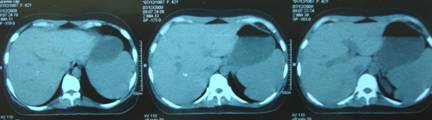

Kết quả chụp CT ổ bụng: gan, lách trong giới hạn bình thường